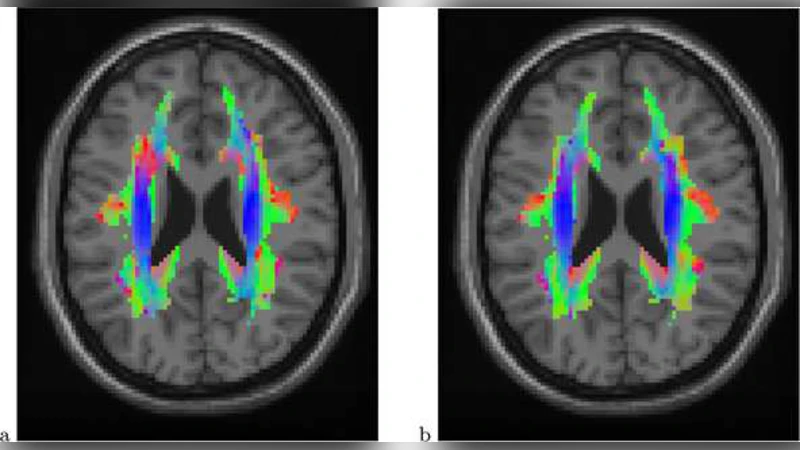

본 연구는 DTI에서 추출한 각 voxel의 주축 확산 방향을 3차원 단위벡터로 표현하고, 이 데이터가 부호 대칭(±x 동일) 특성을 갖는다는 점에 착안해 양극 왓슨(bipolar Watson) 분포를 확률 모델로 채택하였다. 왓슨 분포는 평균 방향 µ와 집중도 파라미터 κ로 정의되며, 밀도함수는 exp(κ(µᵀx)²) 형태로 부호 대칭을 자연스럽게 보장한다. 샘플 평균 방향은 scatter matrix S= (1/n)∑xᵢxᵢᵀ의 최대 고유벡터로 추정하고, 분산은 s=1−γ(γ는 S의 최대 고유값)로 정의한다. 이때 s는 κ⁻¹의 최대우도 추정량에 해당한다.

실험에서는 6명의 정상군과 6명의 난독증군, 총 12개의 확산 방향 지도(95×79×68 voxel)를 사용하였다. 모든 이미지가 MNI 템플릿에 정합(registration)된 후, 백색질 마스크(20,931 voxel) 내에서 분석을 수행했다. 경험적 영가설과 공간 스무딩을 적용한 결과, 기존 FA 기반 분석이 탐지한 120 voxel에 비해 수백 개에 달하는 voxel에서 유의한 방향 차이가 발견되었으며, 특히 상부 좌측 백색질 영역에서 정상군과 난독증군 사이에 뚜렷한 방향 전이 차이가 관찰되었다.